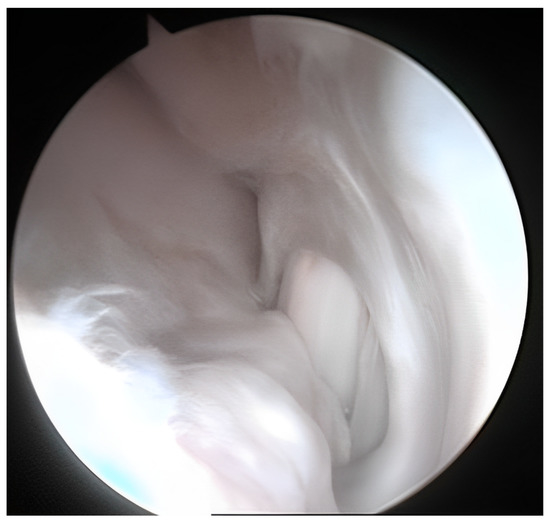

3.2. Arthroscopic Evaluation of the Lesion Site